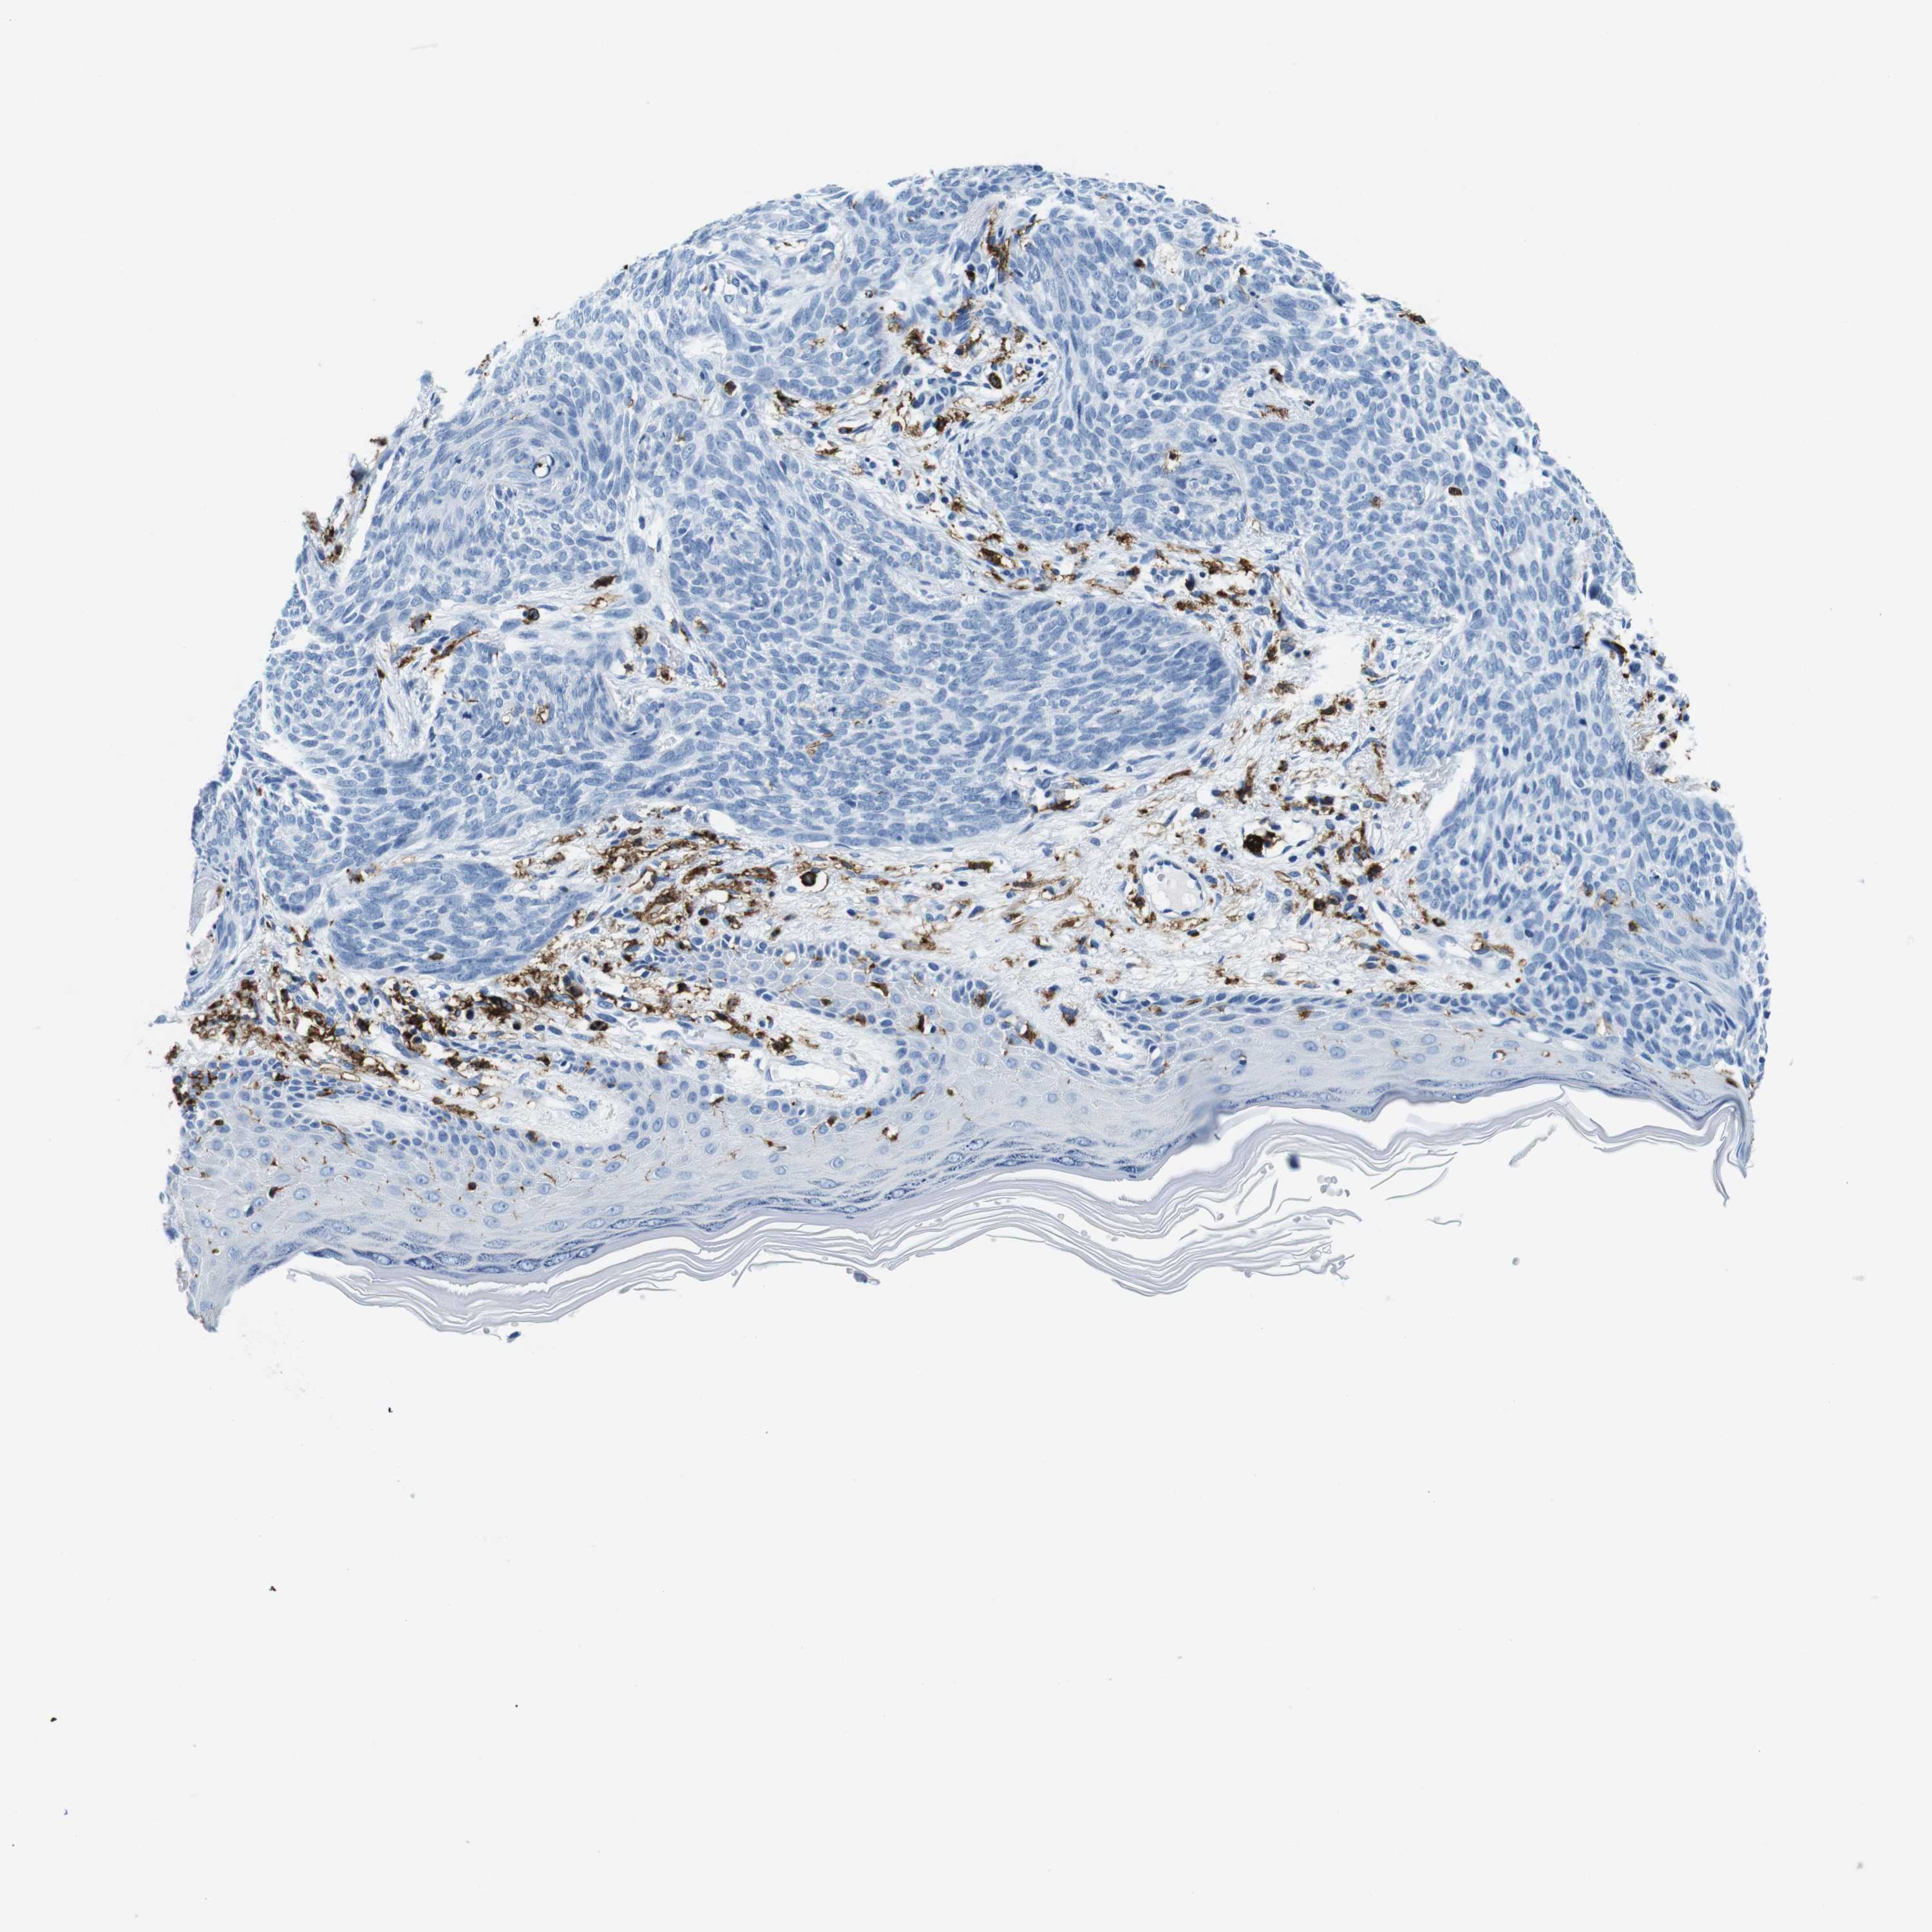

SKIN CANCER - Protein expressioni

A mouse-over function shows sample information and annotation data. Click on an image to view it in a full screen mode. Samples can be filtered based on level of antibody staining by selecting one or several of the following categories: high, medium, low and not detected. The assay and annotation is described here.

Antibody stainingi

Antibody staining in the annotated cell types in the current human tissue is reported as not detected, low, medium, or high, based on conventional immunohistochemistry profiling in selected tissues. This score is based on the combination of the staining intensity and fraction of stained cells.

Each image is clickable and will lead to virtual microscopy that enables deeper exploration of all samples and also displays staining intensity scores, fraction scores and subcellular localization as well as patient and tissue information for each sample.

Antibody HPA043151

Basal cell carcinoma

Squamous cell carcinoma, NOS

Squamous cell carcinoma, metastatic, NOS

Squamous cell carcinoma in situ, NOS

Adnexal tumor, benign